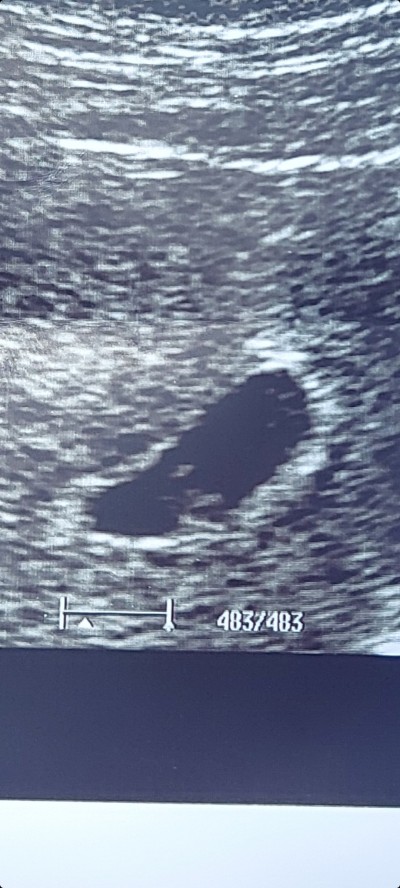

Bakar mısınız burada tek kesede ikiz gebelik mi var

Hayır eşi değil çünkü dikkatli bakıldığında net görünen bebeğin eşi tam onun yanında görünüyor. Doktor ikizden şüphelendi ama net bir şey demedi o yüzden çok merak ediyorum

Bu 7 haftalık

Şimdi 8 oldum, bu resim 7 haftalık ama ikiz olduğu belli değil